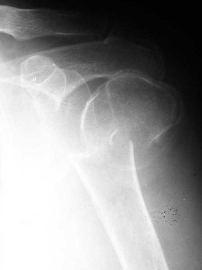

PRE – OPERATORIO

C3

POST – OPERATORIO